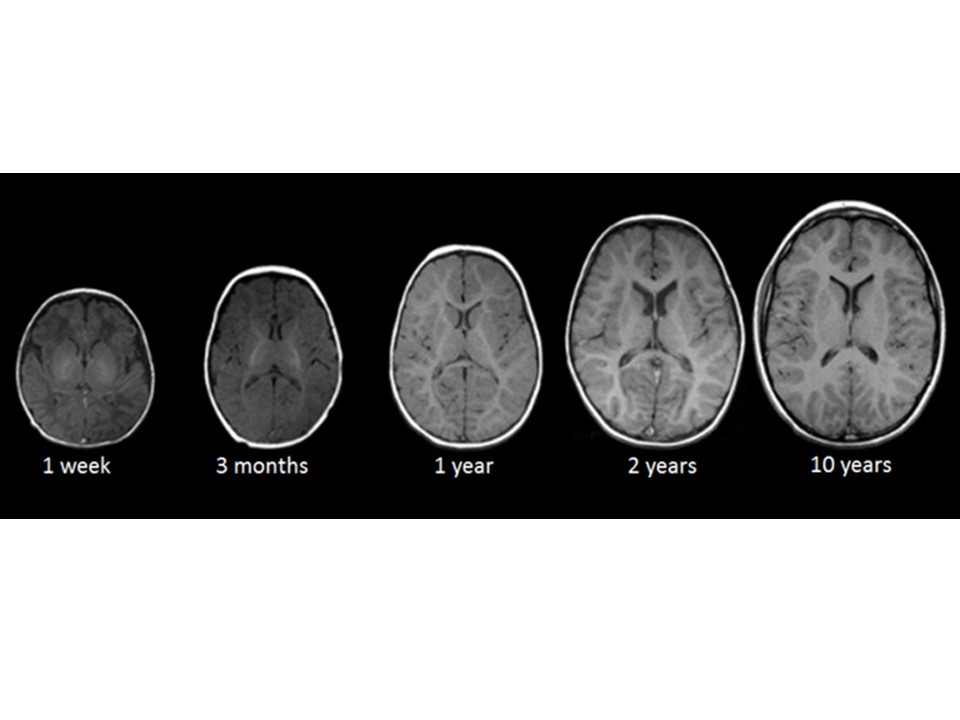

What if this is how we learn?